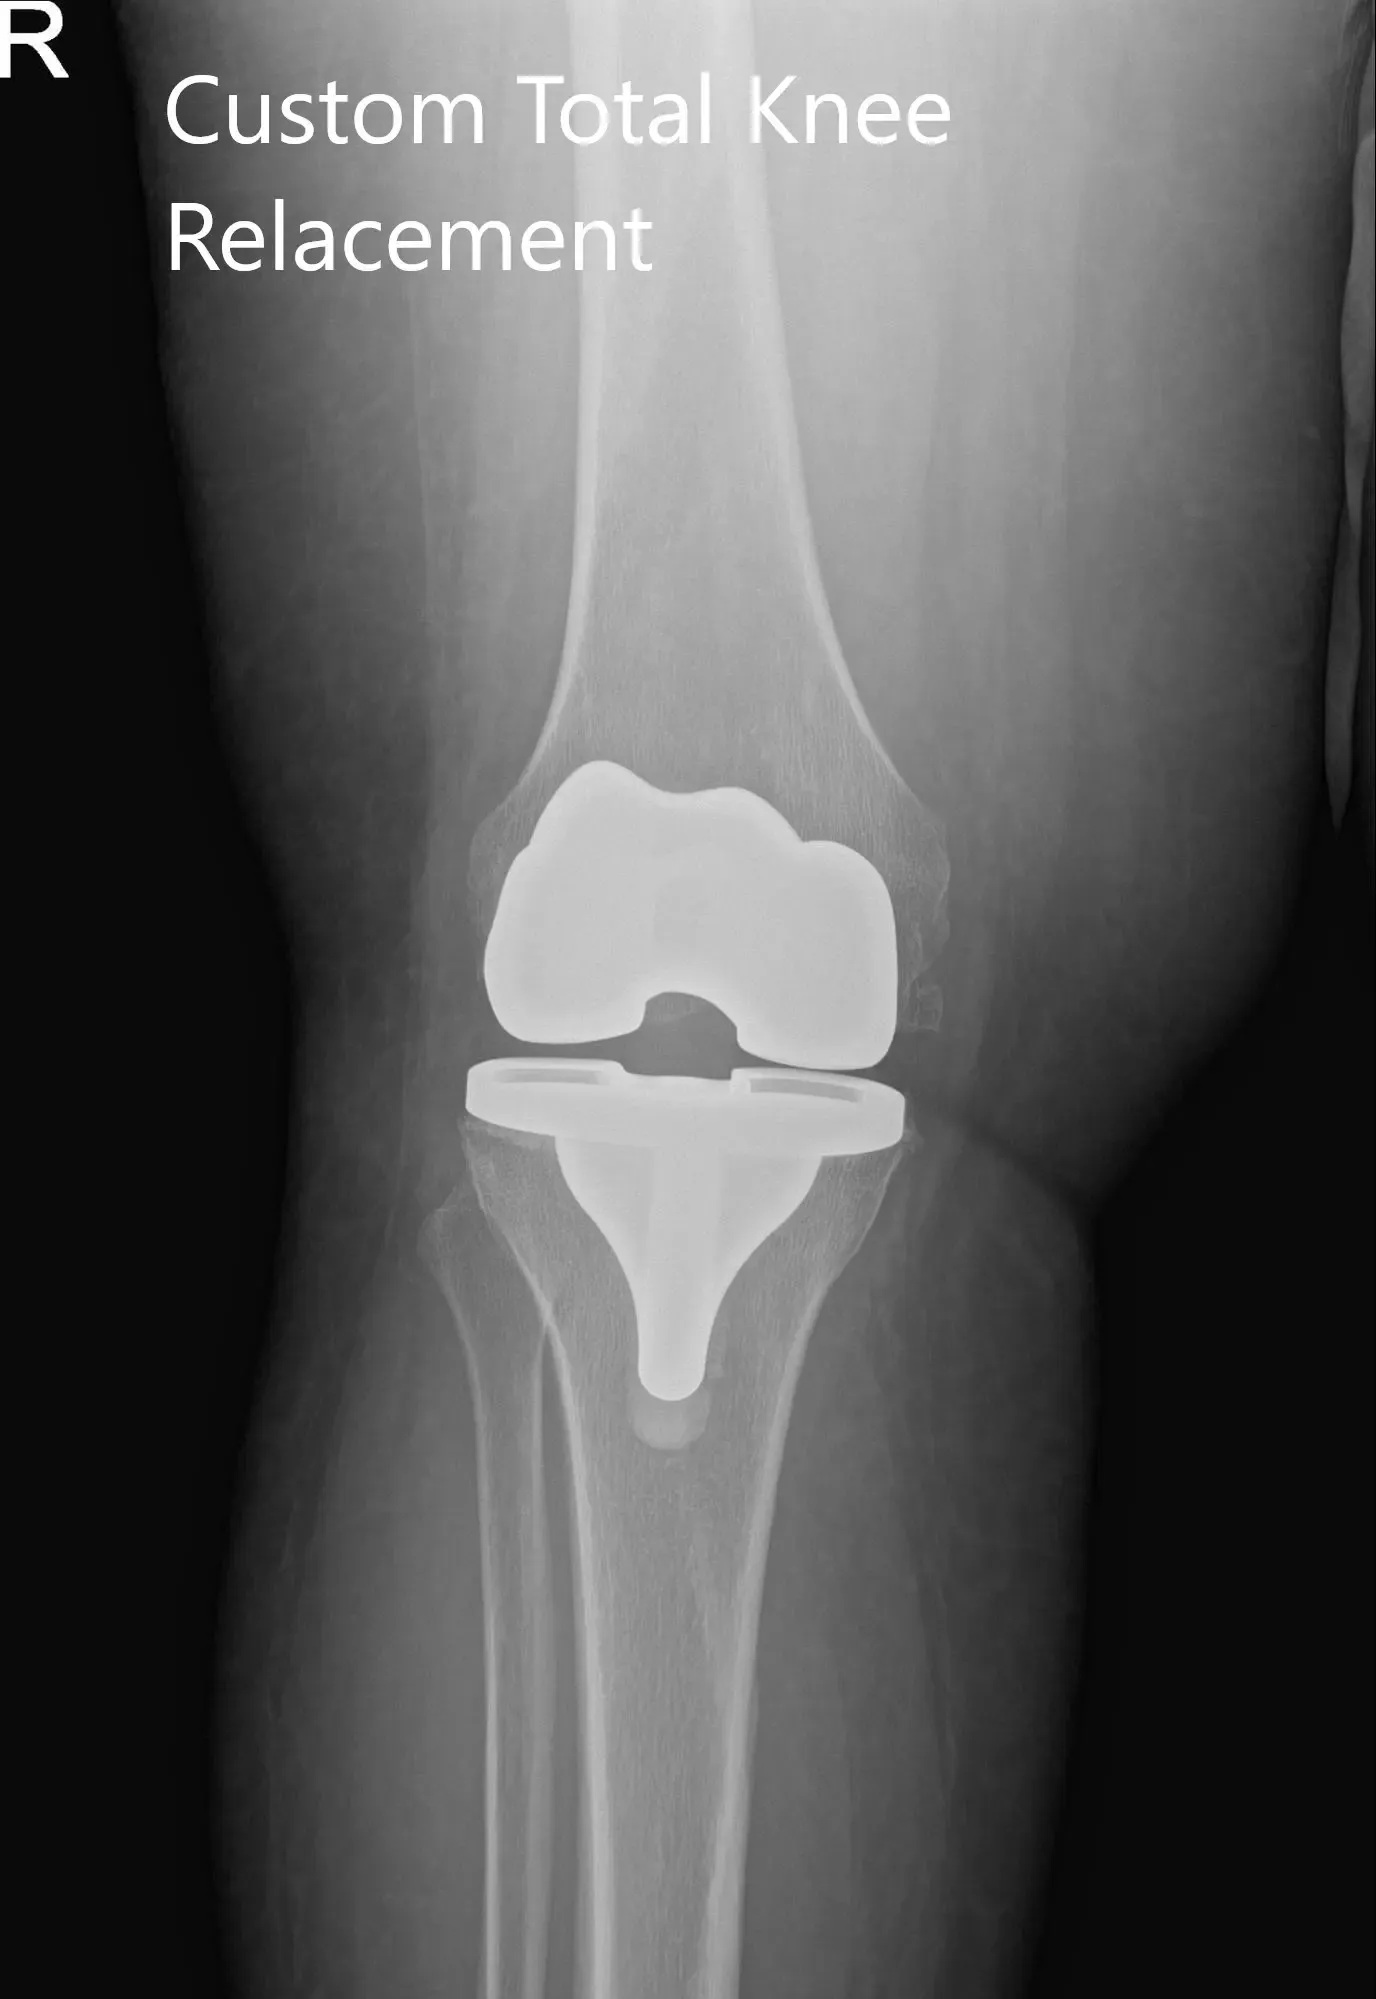

Radiografía postoperatoria de la rodilla derecha del paciente mostrando visión AP y lateral

El paciente pudo soportar peso con apoyo el mismo día de la cirugía. En visitas posteriores, se comprobó que su herida no tenía ninguna infección y se retiraron grapas de la piel tras la cicatrización. Demostró un excelente rango de movimiento de la rodilla en visitas posteriores.

El paciente cumplió con el programa de fisioterapia y ejercicio en casa. Mostró un rango completo de movimiento, que no tuvo dolor en una revisión de 3 meses. Afirmó que podía conducir un coche, subir escaleras y jugar con sus nietos sin la ansiedad de provocar el dolor. El paciente afirmó que experimentó una mejora en la calidad del sueño y pudo retomar su trabajo como agente penitenciario. El paciente ha vuelto ahora a las actividades que disfrutaba antes del proceso de la enfermedad.